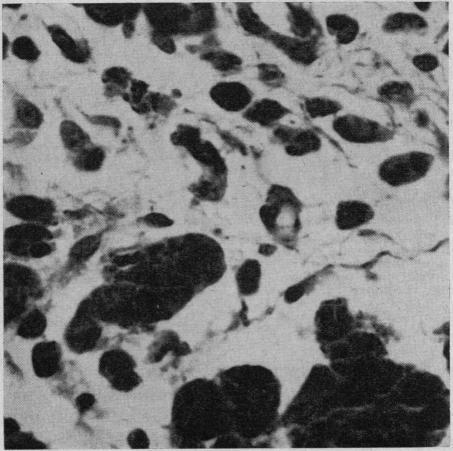

Chemical synovectomy of an experimental arthritis.

Can Med Assoc J. 1969 Jul 12;101(1):24-9.